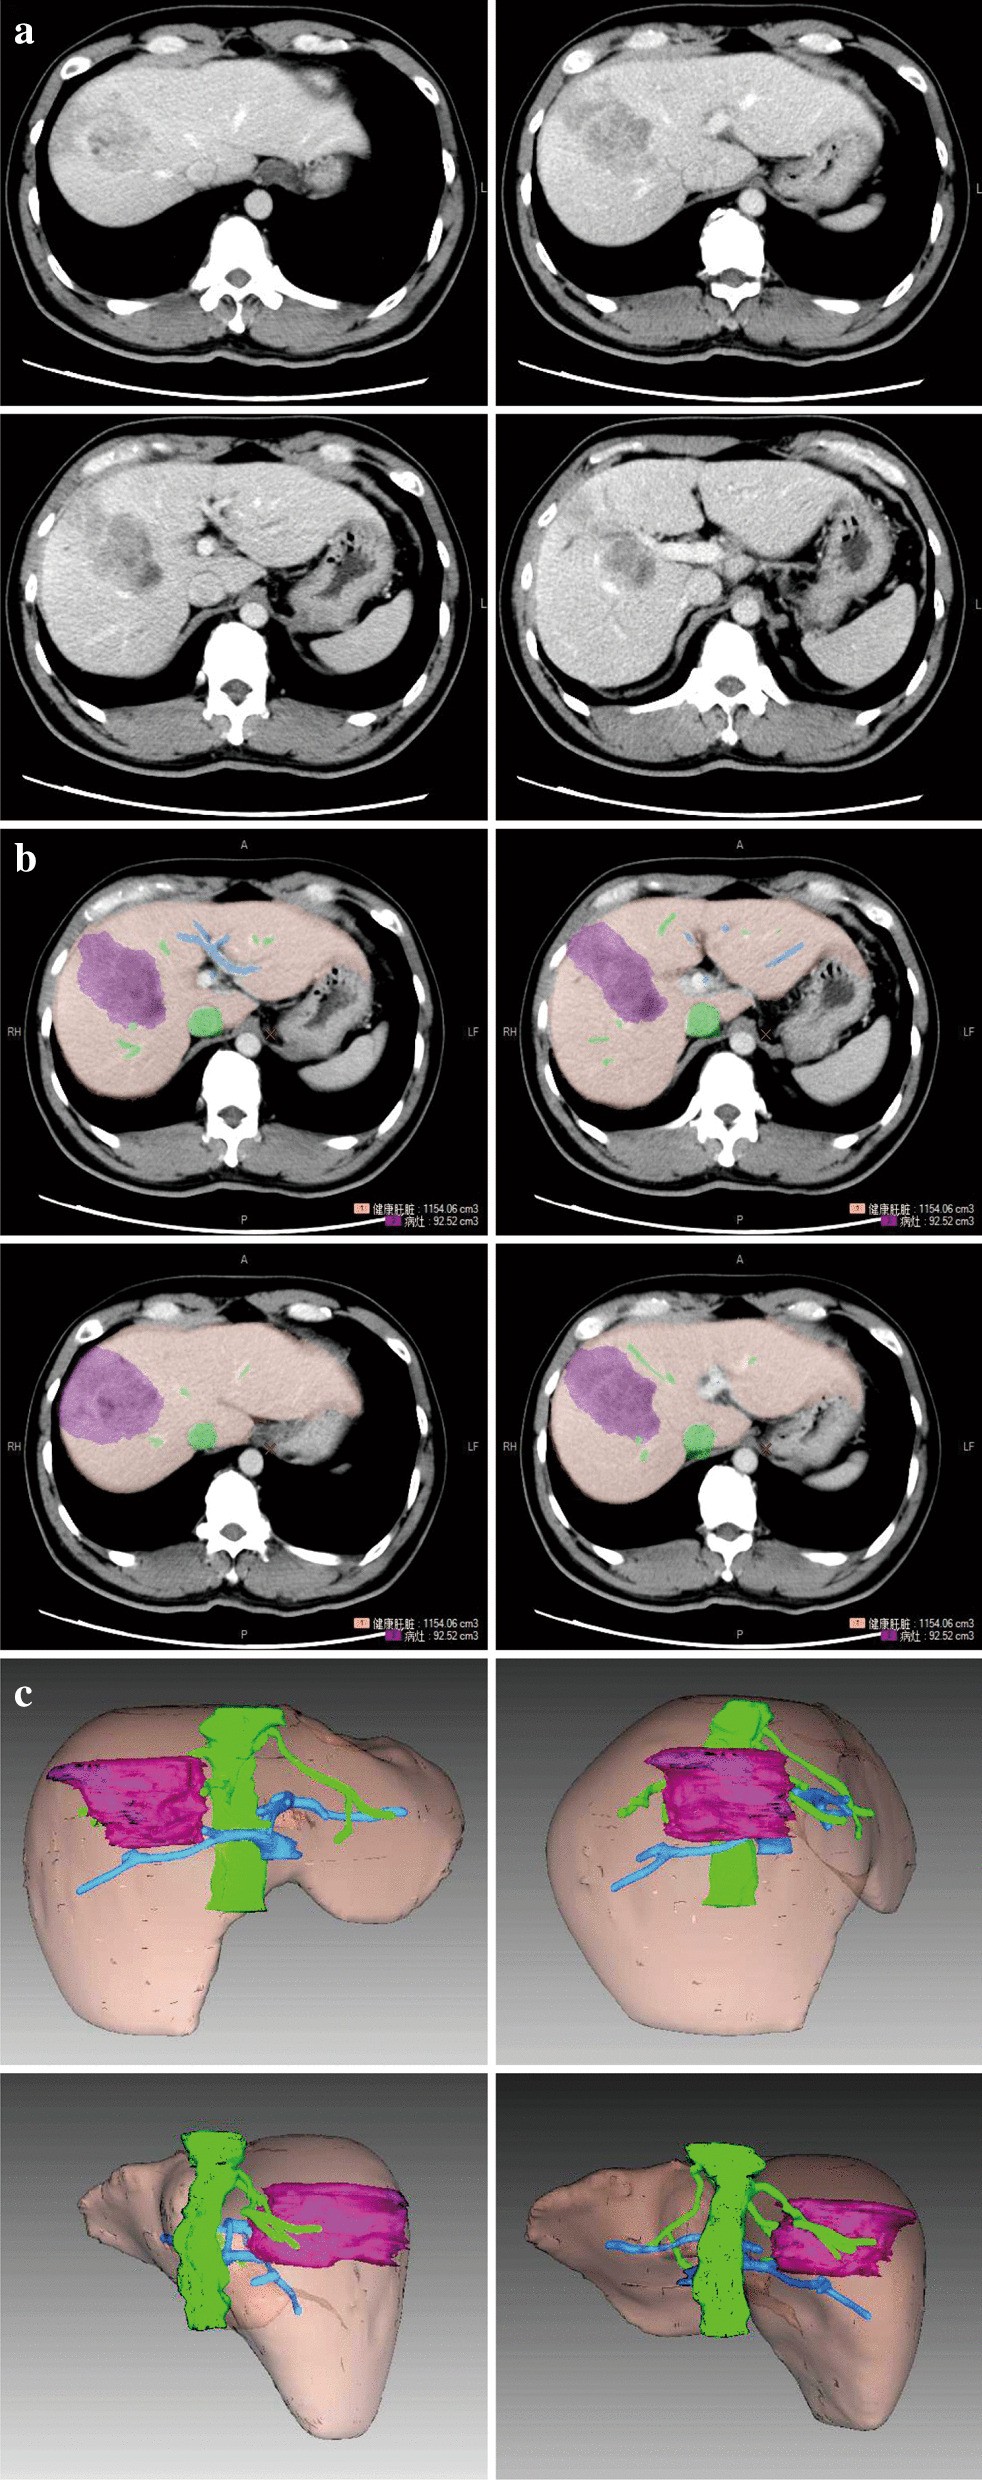

Fig. 1From: Safe standard remnant liver volume after hepatectomy in HCC patients in different stages of hepatic fibrosisRepresentative micrographs showing a portal venous phase; b contours of liver, tumour, hepatic vein and portal vein depicted with different colours; and c 3D reconstruction of liver, tumour, hepatic vein and portal veinBack to article page